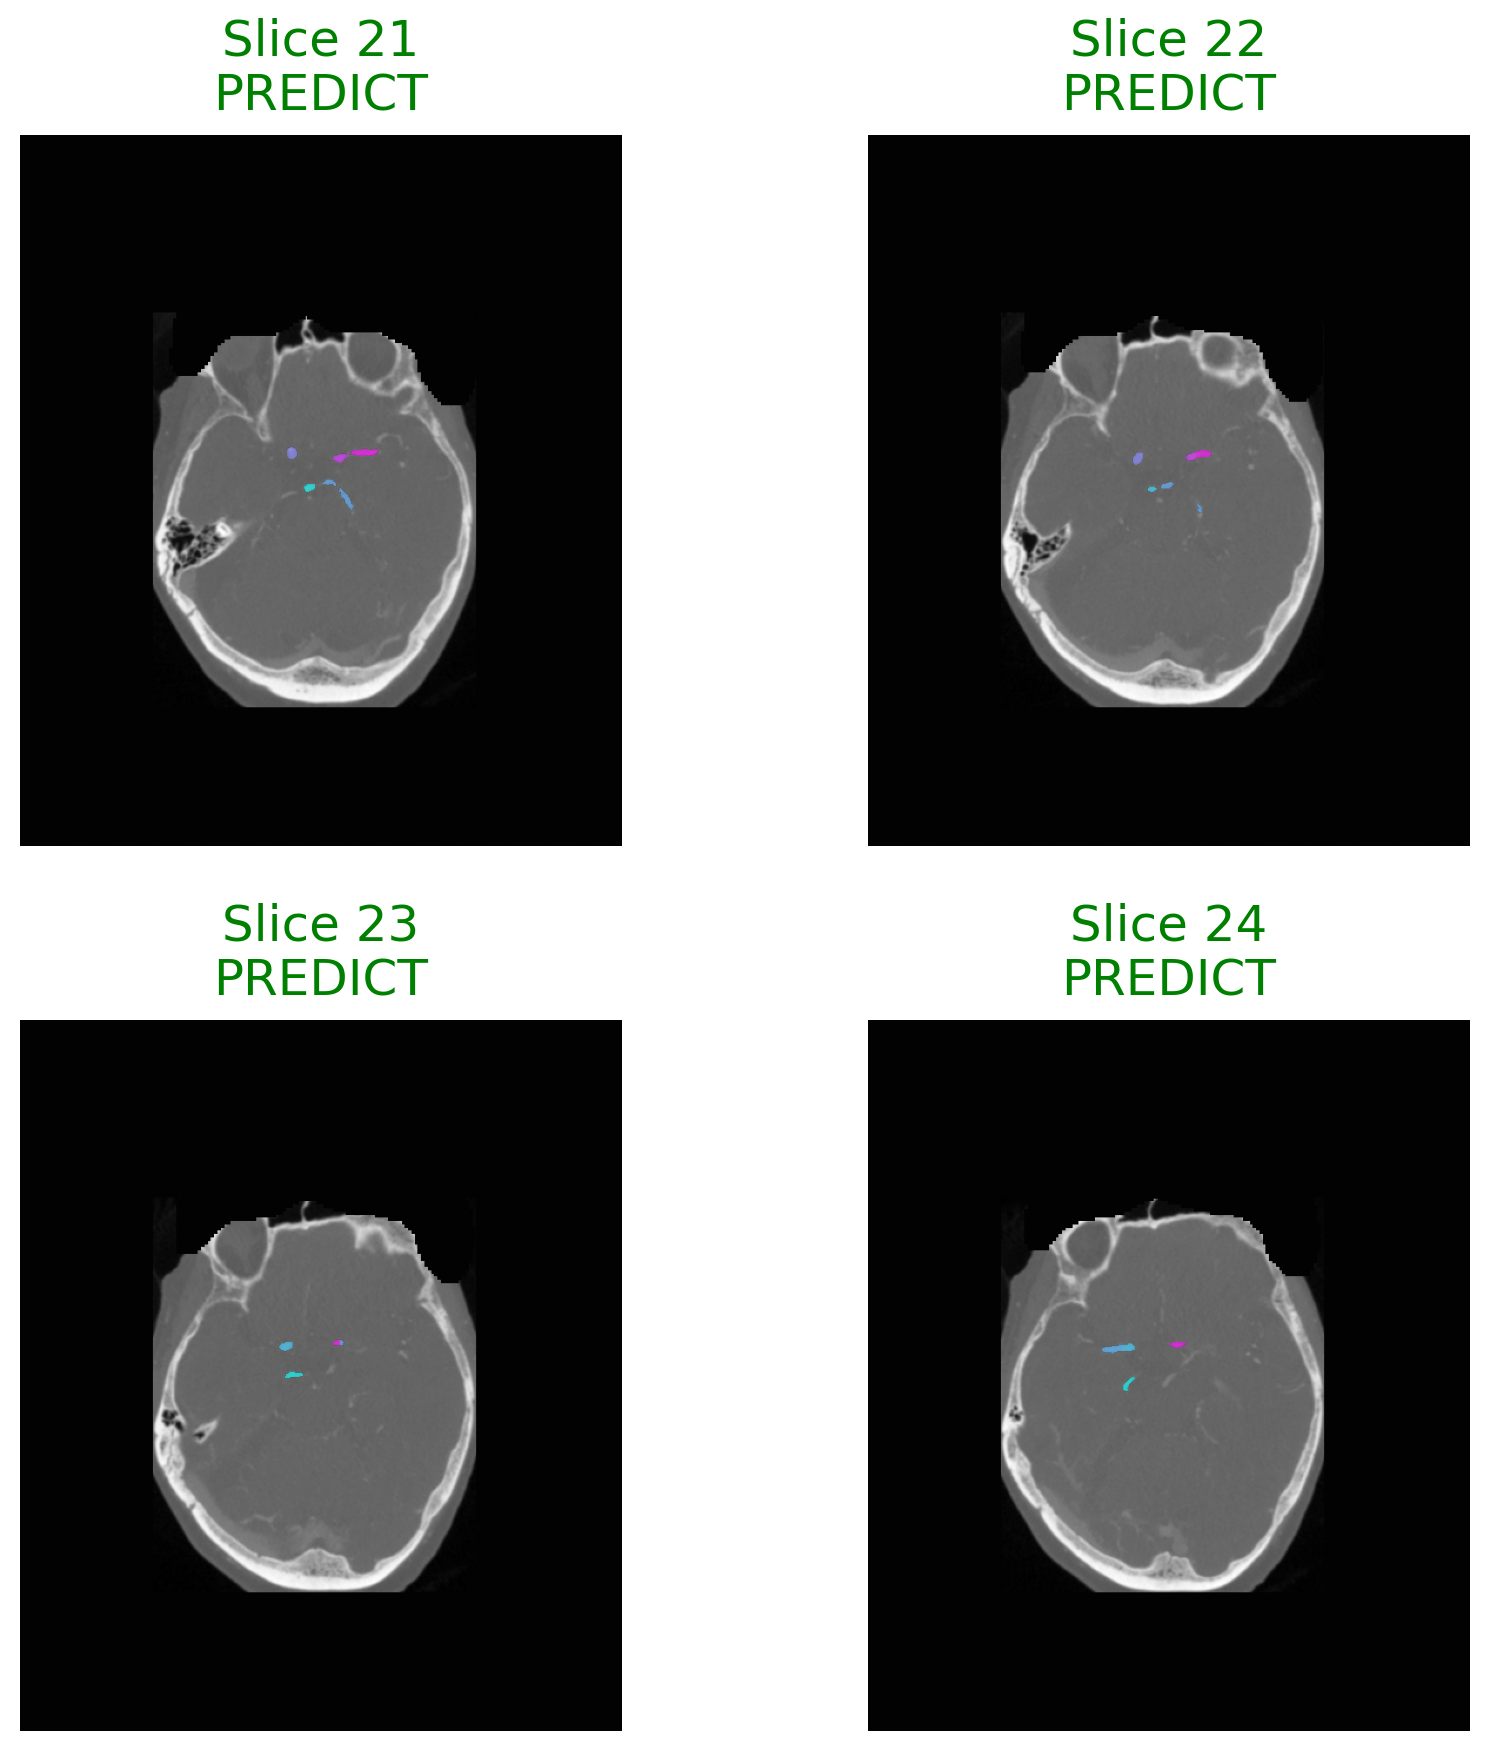

An Explainable Agentic AI Framework for Uncertainty-Aware and Abstention-Enabled Acute Ischemic Stroke Imaging Decisions

Artificial intelligence models have shown strong potential in acute ischemic stroke imaging, particularly for lesion detection and segmentation using computed tomography and magnetic resonance imaging. However, most existing approaches operate as black box predictors, producing deterministic outputs without explicit uncertainty awareness or structured mechanisms to abstain under ambiguous conditions. This limitation raises serious safety and trust concerns in high risk emergency radiology settings. In this paper, we propose an explainable agentic AI framework for uncertainty aware and abstention enabled decision support in acute ischemic stroke imaging. The framework follows a modular agentic pipeline in which a perception agent performs lesion aware image analysis, an uncertainty estimation agent computes slice level predictive reliability, and a decision agent determines whether to issue a prediction or abstain based on predefined uncertainty thresholds. Unlike prior stroke imaging systems that primarily focus on improving segmentation or classification accuracy, the proposed framework explicitly prioritizes clinical safety, transparency, and clinician aligned decision behavior. Qualitative and case based analyses across representative stroke imaging scenarios demonstrate that uncertainty driven abstention naturally emerges in diagnostically ambiguous regions and low information slices. The framework further integrates visual explanation mechanisms to support both predictive and abstention decisions, addressing a key limitation of existing uncertainty aware medical imaging systems. Rather than introducing a new performance benchmark, this work presents agentic control, uncertainty awareness, and selective abstention as essential design principles for developing safe and trustworthy medical imaging AI systems.

paper research